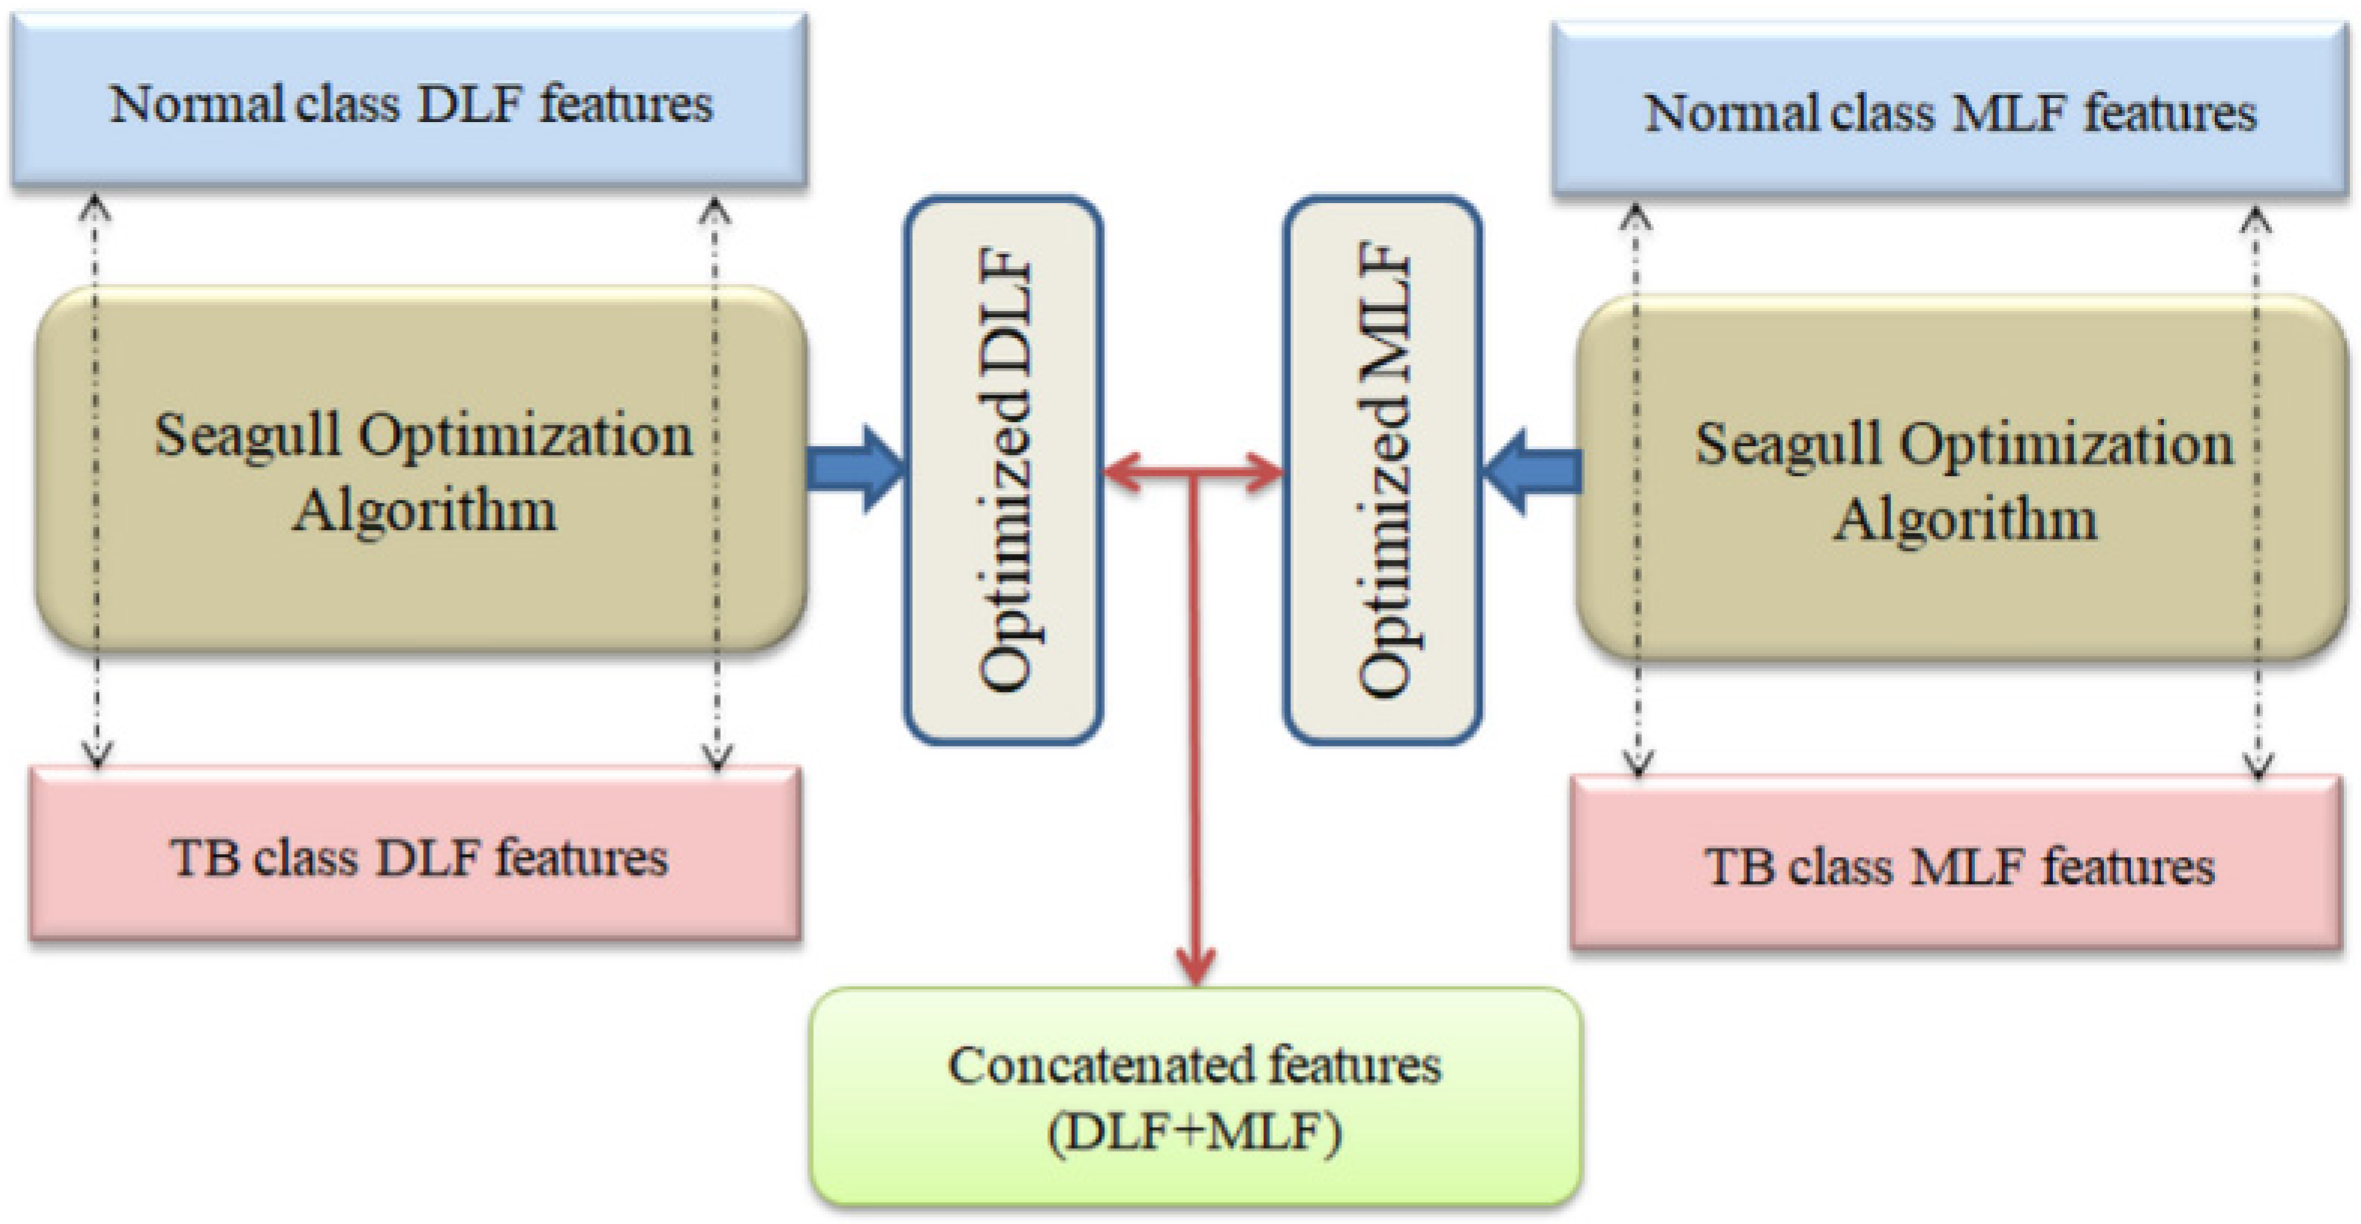

- (i)

- Implementation of pre-trained DLS-based TB detection from chest X-ray;

- (ii)

- Generation of MLF using LBP and DWT;

- (iii)

- SA-based feature optimization and serial feature concatenation to obtain DLF+MLF.

3.4. Seagull-Algorithm Based Feature Optimization